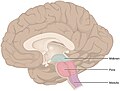

Brain: Lateral view

Schematic overview (WC/blausen staff)

- Basal ganglia 1.jpg

Section with descriptions (WC/SMH)

- Uncus (as in uncal herniation).

- Brain stem = medulla oblongata, pons, mesencephalon (midbrain).[1]